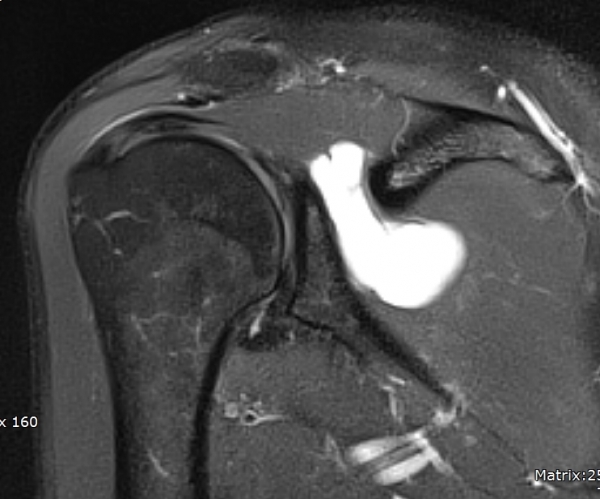

¾î±ú µÚÂÊ È¾´Ü¸é°Ë»ç¿¡¼­ °üÀý¿Í(glenoid) ³»Ãø¿¡¼­ ¸¹Àº ¾çÀÇ ¼ö¾×Àú·ù°¡ °üÂûµÈ´Ù(»çÁø 1, 2).

ÀÚ±â°ø¸í°Ë»ç

large paralabral cyst